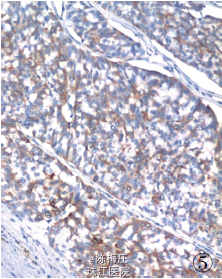

最后诊断:右乳神经内分泌癌;结肠腺癌;左侧卵巢Brenner 瘤。 遂行右乳肿物切除术+ 乙状结肠癌切除术及左侧附件切除术。术中所见:右乳肿物分叶状,与周围界清;乙状结肠肿物与周围无粘连;左侧卵巢肿物包膜完整,未见腹水。术后病理显示右乳腺内分泌癌,乙状结肠腺癌,左侧卵巢Brenner 瘤。